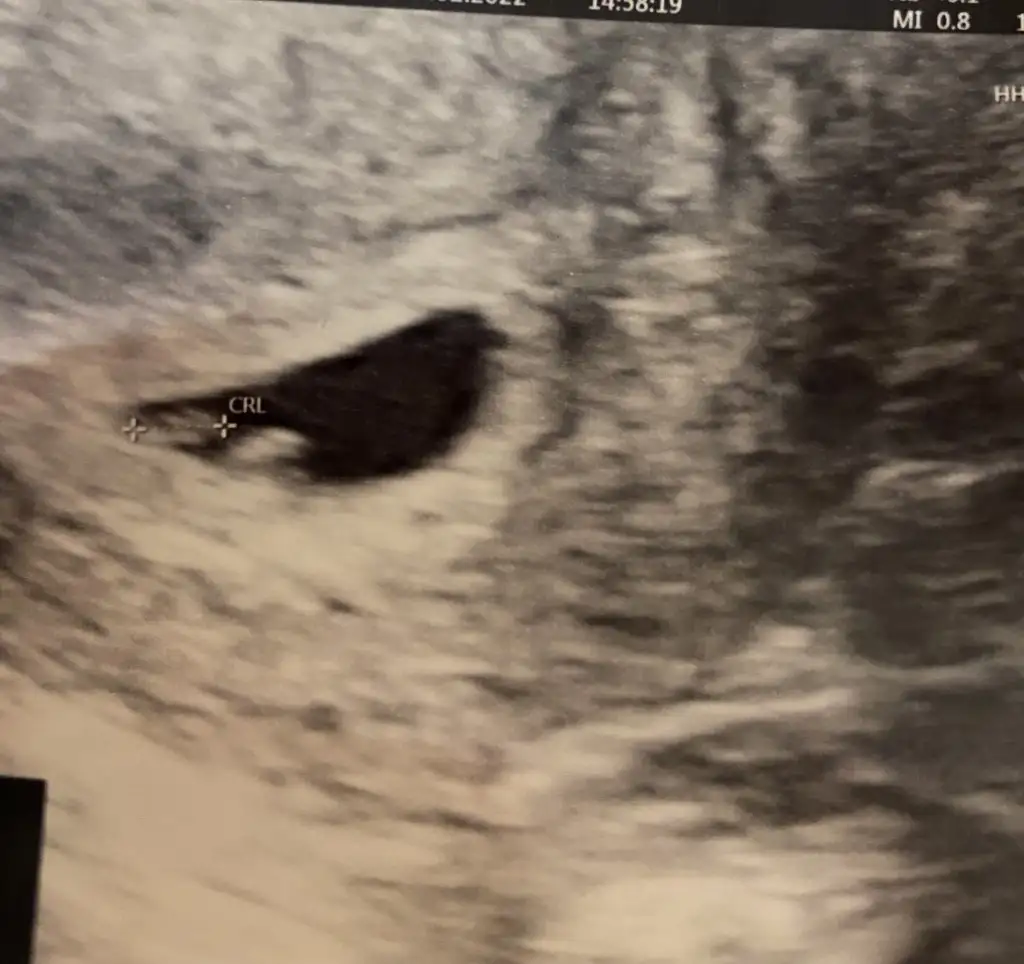

Benimkine de tahminde bulunur musunMerhaba millet

Ramzi teorisine göre cinsiyet tahmini yapacagim ilk ultrasyon resminizi atin bakiyim. Eger cinsiyetiniz belliyse hic söylemeeyin bakalm dogru tahmin edebilecekmiyim daha dogrusu ramzi teorisi hakli cikacak mi?

Benim görüntüleme bakarmisiniz 6 haftalik karından ultrasonKiz diyorum